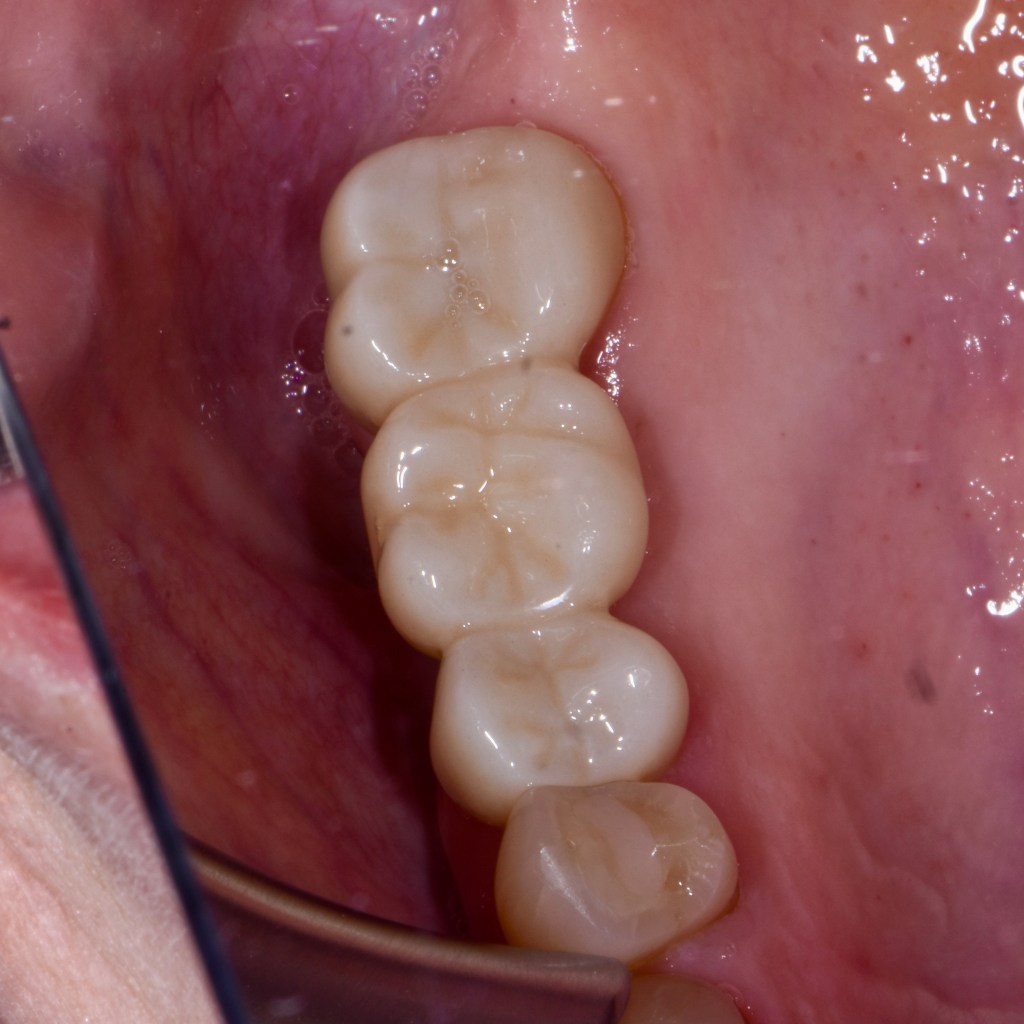

Custom Ceramic Crown

Custom Ceramic Crowns